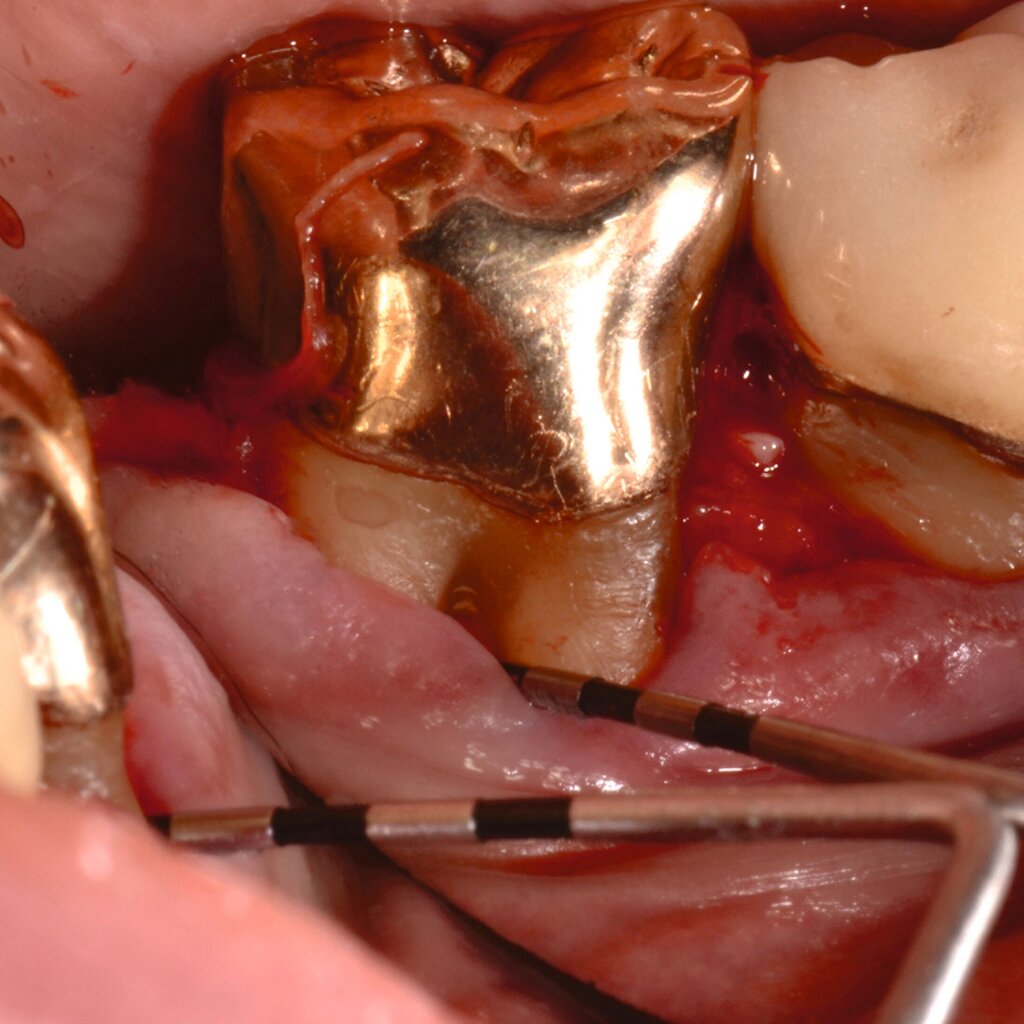

Fall 3 – komplex